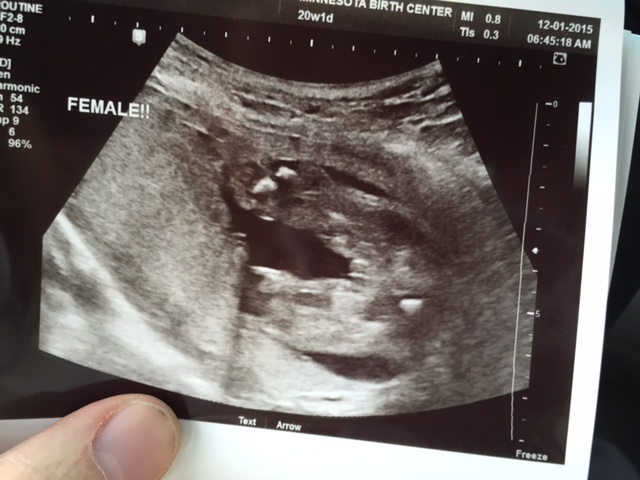

UPDATE!!! It's a girl -- confirmed at 20wks!!! Can't really believe it quite yet. So happy!!!! DS1 is thrilled to have a little sister (did not want another bro, lol). DS2 doesn't want either a lil sis or bro. Ha.

Attachment 28762 Attachment 28763